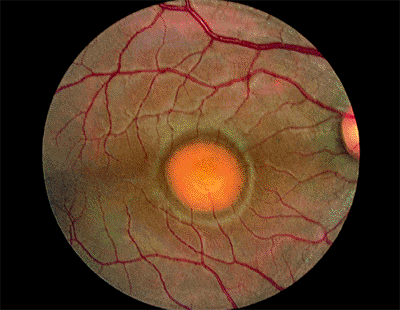

Медицинские исследования: эластическая псевдоксантома